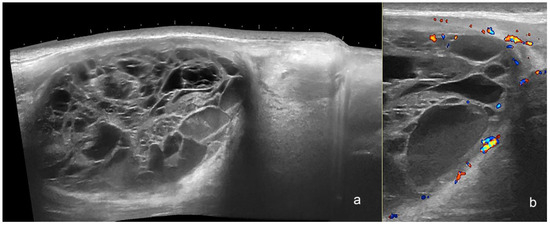

3. Dermatofibrosarcoma Protuberans (DFSP)

| Dermatofibrosarcoma Protuberans | heterogeneous, hypoechoic on the surface and/or intermediate parts, and hyperechoic at the bottom with pseudopods or jellyfish-like, tentacle, or claw signs | intermediate degree |